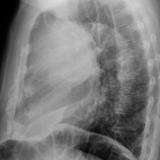

Case 8b Thymoma Lat

Date: 03/27/2009

Views: 14171